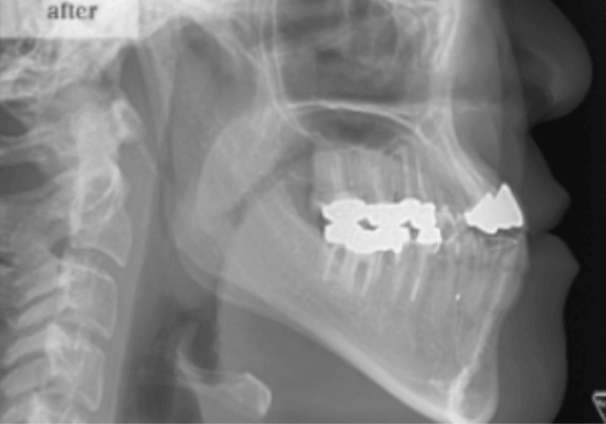

40代女性:反対咬合の治療(ゴムメタル矯正)Skeletal Class Ⅲ Mesio-fecial Type Case

治療後